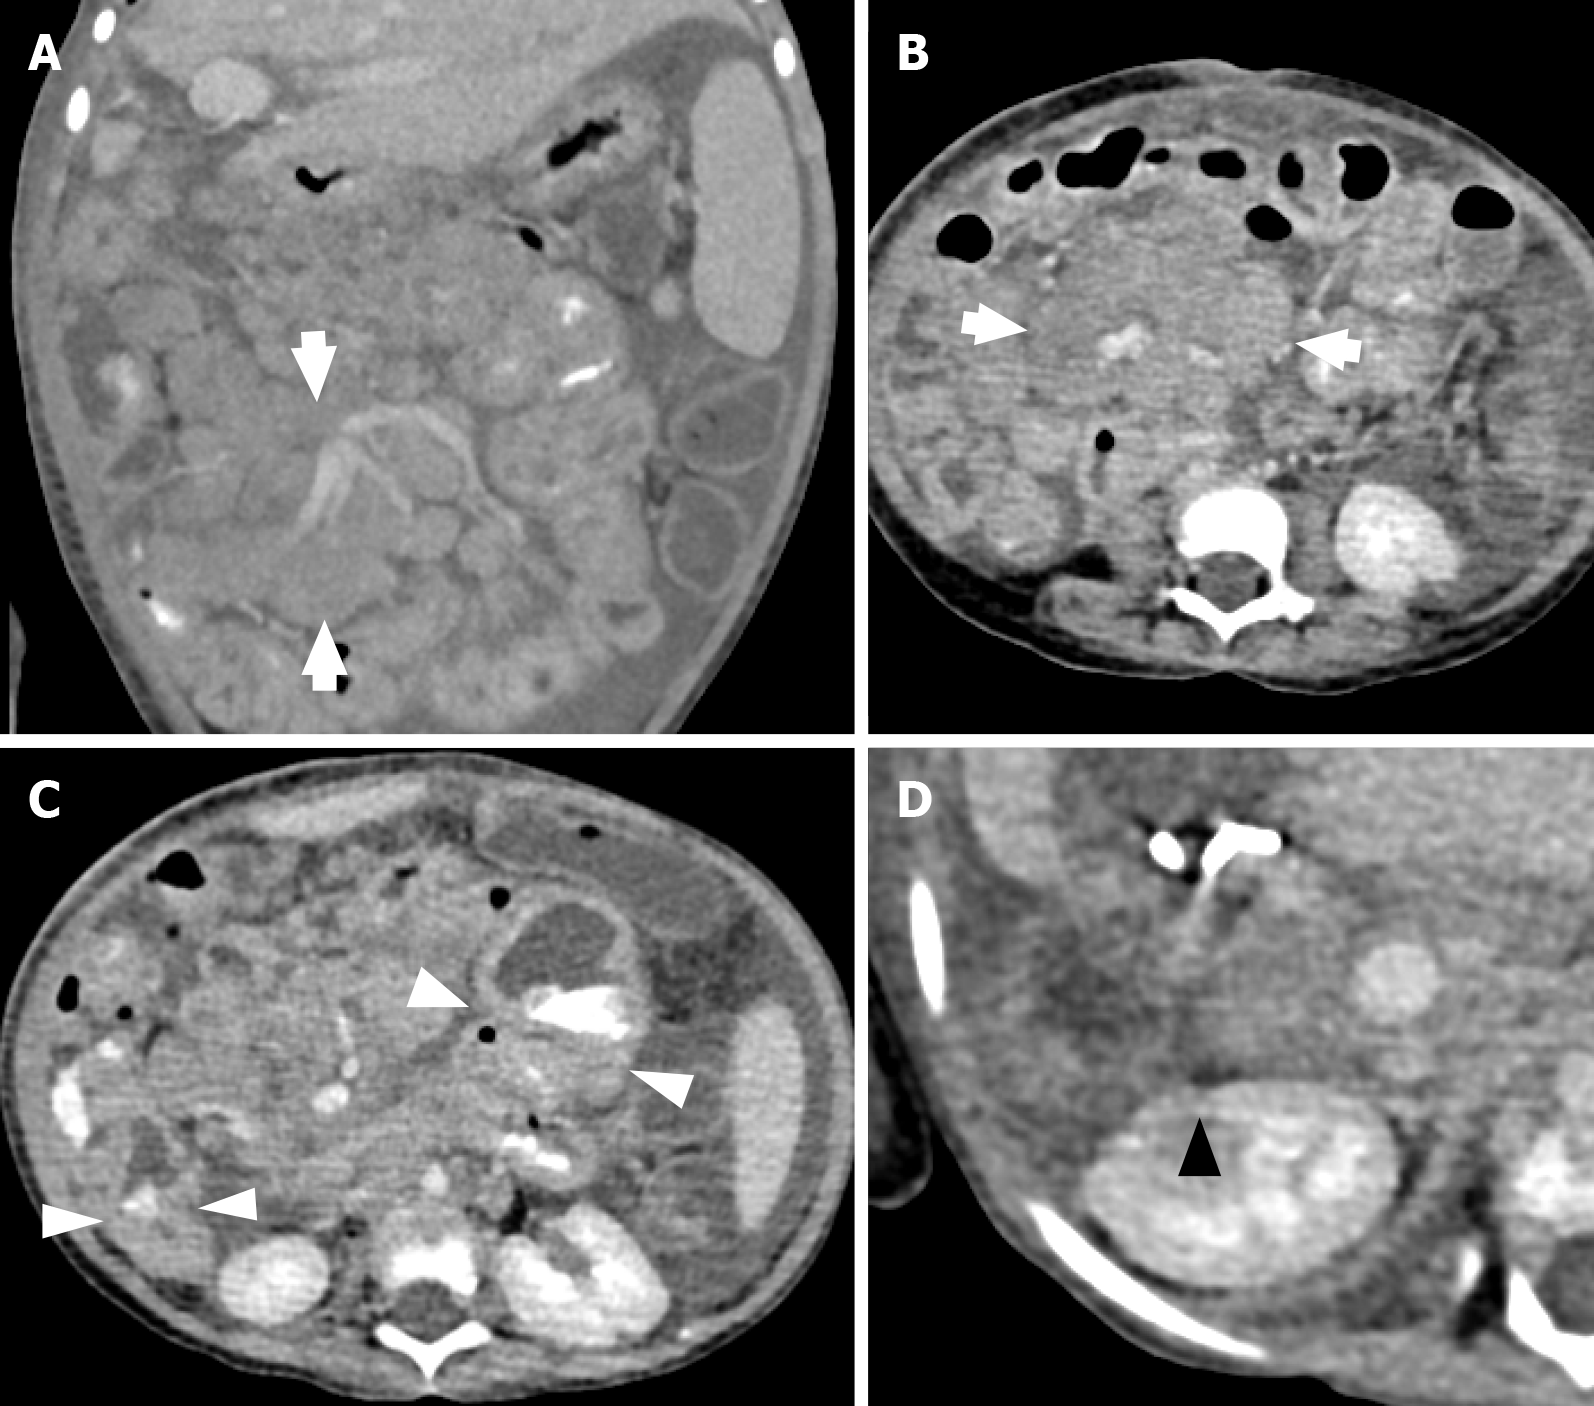

Figure 5 Computed tomography images.

A and B: Computed tomography images of a 34-month-old girl who presented with pallor and mucous diarrhea after liver transplantation showed large, matted mesenteric lymph nodes (white arrows); C: A few small bowel loops with focal wall thickening (white arrowheads); D: A hypoenhancing lesion in the right kidney (black triangle).